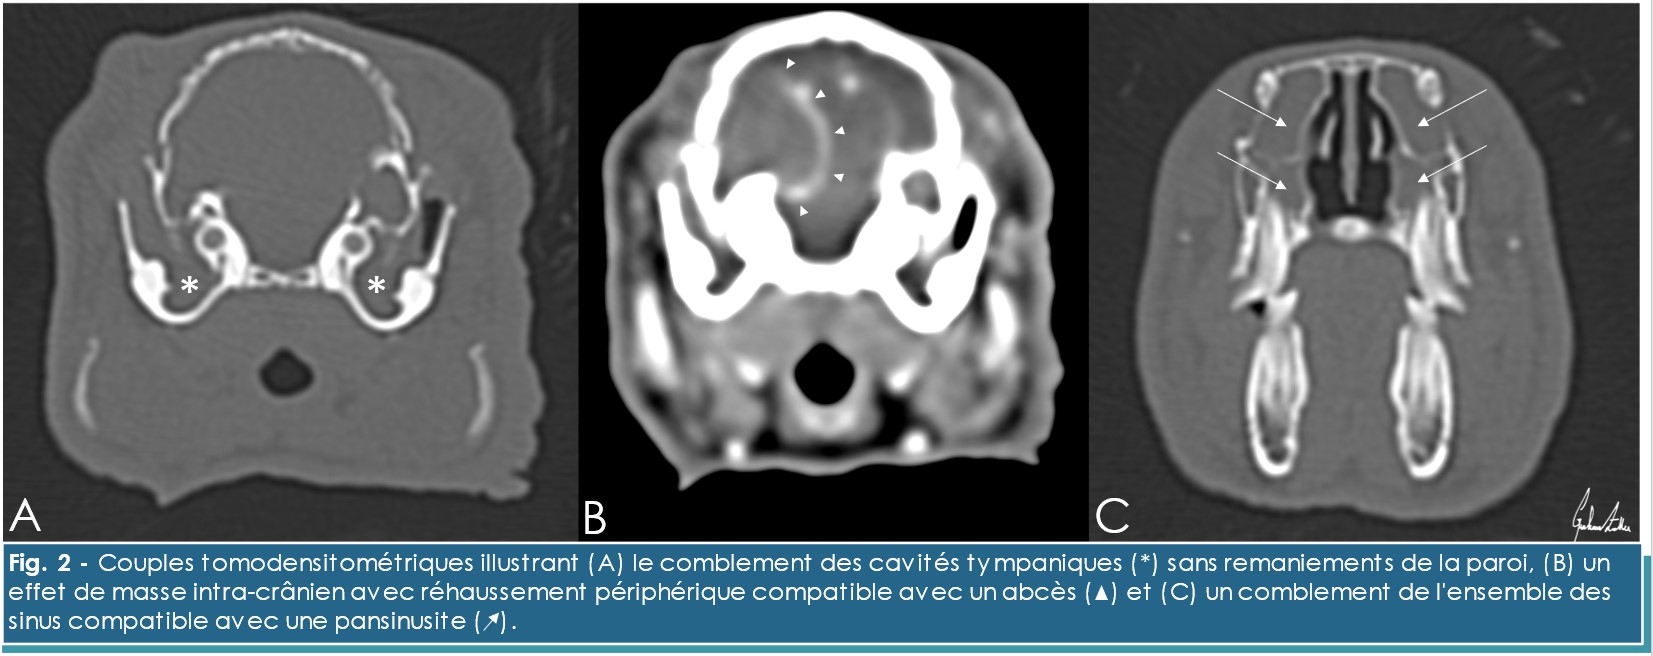

Dans notre cas, l’examen tomodensitométrique révèle une bulle tympanique d’apparence normale et associée à un comblement bilatéral de la cavité tympanique par un matériel hypoatténuant ne réhaussant pas suite à l’administration de produit de contraste. (Figure 2.A) Cette situation est prioritairement compatible avec une otite moyenne/interne de grade 2.17 Le scanner permet d’évaluer l’extension de l’infection et indique un comblement des canaux auriculaires externes bilatéralement, la présence d’un effet de masse intracrânien à réhaussement périphérique, prioritairement compatible avec un abcès, (Figure 2.B) et un comblement de l’ensemble des récessus paranasaux (pansinusite) (Figure 2.C). La culture bactérienne ne permet pas l’identification de la bactérie responsable. Une sérologie E. cuniculi est réalisée compte-tenu de la fréquente co-existence de ces deux maladies et révèle un titre anticorps incompatible avec une exposition.3